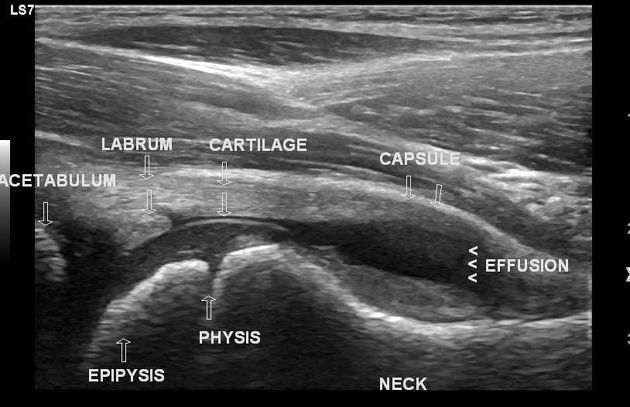

2. 초음파 소견

관절 주위 연부조직과 관절내 삼출액 유무를 확인할 수 있습니다. 대퇴 경부 전방에서 장요근의 후방까지의 거리를 측정하여 2mm 이상 증가한 경우를 활액 증가 소견으로 볼 수 있습니다.